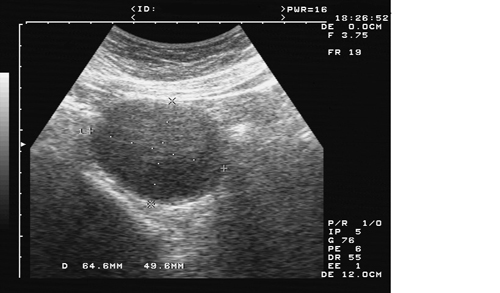

巧克力囊肿,顾名思义,就是囊肿里头的东西就像粘稠的巧克力液一样,实际上是陈旧的血液,这是一种子宫内膜异位的一个表现。这种囊肿可能是因为经血没有能够顺畅的从阴道流出去,它逆流了,逆流到卵巢上了,就成一个包了,这叫巧克力囊肿。

卵巢巧克力囊肿随着病程的延长,囊肿内积血的不断增加,囊肿体积也随之增大。当囊腔内积血过多、压力过高时,可撑破囊壁薄弱部分,发生囊肿自发性破裂,囊内流出部分积血,压力降低后,囊壁破口常可自行愈合。经过若干时间后,囊内积血再次增多、压力再次增大时,又可发生自发性破裂。囊肿破裂后流至盆腔内的积血,刺激腹膜,引起剧烈腹痛,并可造成盆腔器官的粘连。卵巢巧克力囊肿可以在没有诱因情况下自发破裂,粗暴或剧烈的*生活性**,尤其是经前期*生活性**,常是常见的导致囊肿破裂的重要诱因。